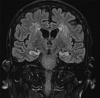

(图一、第31天MRI头显示双侧海马和脑室周围高强度。)

在第+24天,他的ICE分数进一步下降到6/10,简易精神状态检查(MMSE)评分为12/30。由于神经毒性复发,患者重新开始服用地塞米松。尽管重新开始使用类固醇,但他的认知功能继续下降,特别是有证据表明有顺行性和逆行性失忆症。因此开始对疑似脑膜脑炎使用大剂量阿昔洛韦静脉注射和广谱抗生素。在此期间,他的CRP保持在低水平(最近使用了托西珠单抗),并发急性重度低钠血症(最低为116 mmo/L),渗透性提示潜在的SIADH。仍然存在严重的细胞减少症。患者因急性低钠血症和认知状态恶化再次入院接受重症监护。他开始使用高渗盐水,并继续使用广谱抗菌剂。第31天进行MRI头部检查(图1),发现对称T2/FLAIR型高信号伴相关的受限扩散,涉及整个海马体、头部和杏仁核。这在他+28日的 PET扫描中也得到了证实,该扫描也发现了一个完全的代谢反应,在以前疾病部位的残留软组织中无法检测到摄取,但注意到对称的、强烈的海马回信号,与MRI异常相对应。这两种变化都与脑炎过程相一致。